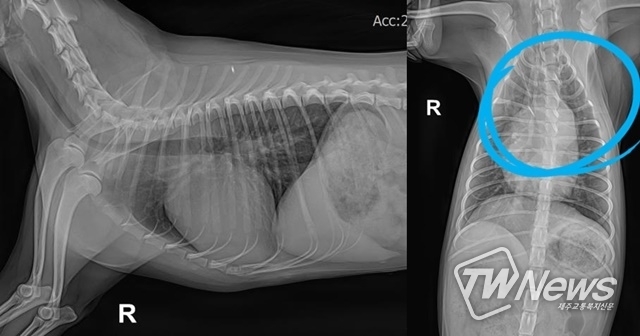

환자를 입양했을 때, 혹은 위의 증상이 나타난다면 동물병원에서 기본적인 신체검사, 방사선 및 청진을 통한 심 잡음 검사를 받고 필요시에는 심장 초음파를 진행해야 한다. 사례마다 동맥관의 형태가 다르기 때문에 수술 전에 CT 촬영을 통해 형태를 확인한 뒤에 두 가지 방법 중 더 적절한 방법을 선택해 수술을 진행해야 한다.